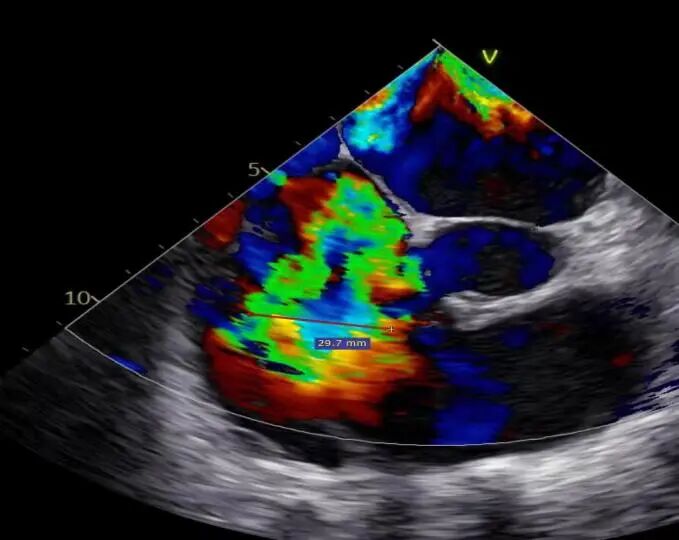

二尖瓣术前评估

复查TTE及TEE检查进一步评估二尖瓣情况。明确为FMR( Carpentier Ⅲb型),二尖瓣后叶栓系,2区瓣叶运动(视频2),重度FMR(4+), 肺静脉逆向血流;2区后叶长度1.15cm,2区前叶长度2.46cm,AP径3.2cm,瓣口面积5.1cm²,房间隔高度3.95cm,瓣叶无钙化,二尖瓣瓣膜条件适合行TEER手术。

图1、图2:2区瓣叶长度(前叶长度2.46cm,后叶长度1.15cm)及彩色血流